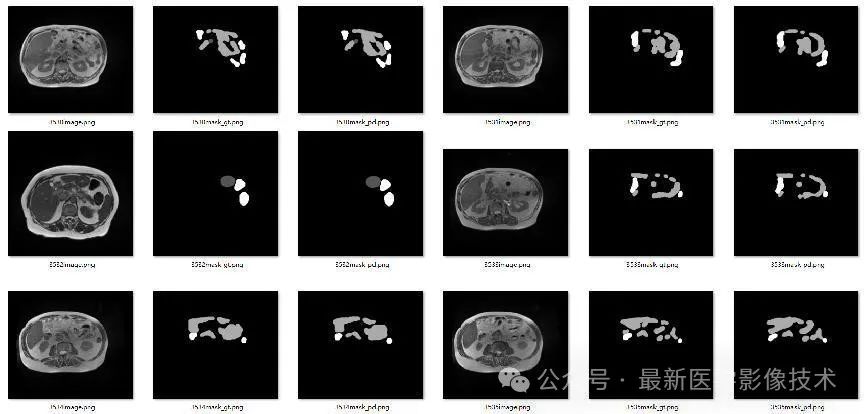

4、验证集部分分割结果